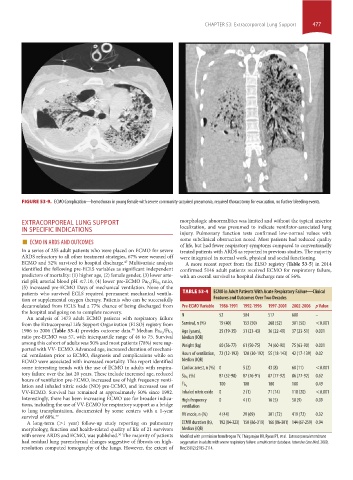

FIGURE 53-9. ECMO Complication—hemothorax in young female with severe community-acquired pneumonia, required thoracotomy for evacuation, no further bleeding events.